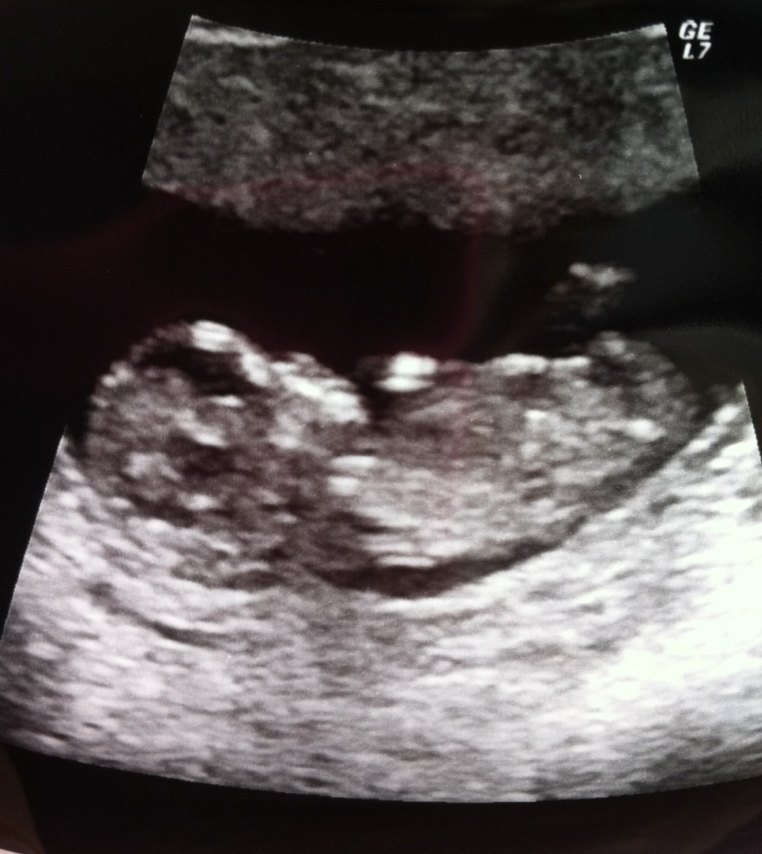

Jeg er glad og stolt, det var en vild oplevelse at se den lå og hoppede rundt og hjertet bankede!.

Ja, og så se at det faktisk er en baby. Det ligner jo virkelig et lille mennesker der ligger derinde, og i ugerne inde har det ikke helt så meget form, hvis man overhoved er blevet scannet tidligere.